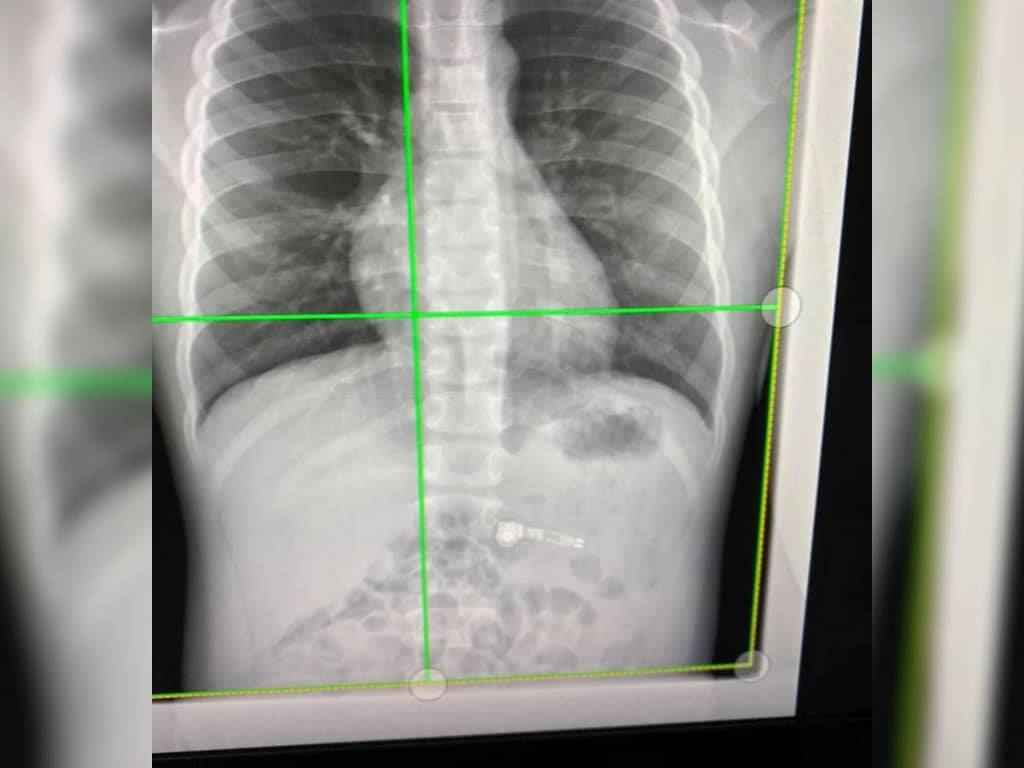

X-rays shows the wireless headphone inside the body.

An X-ray image taken at Children's Healthcare of Atlanta, Georgia displayed the device resting peacefully inside the boy's stomach, reports WSB-TV.

X-rays showed the wireless headphone was still intact inside the body.